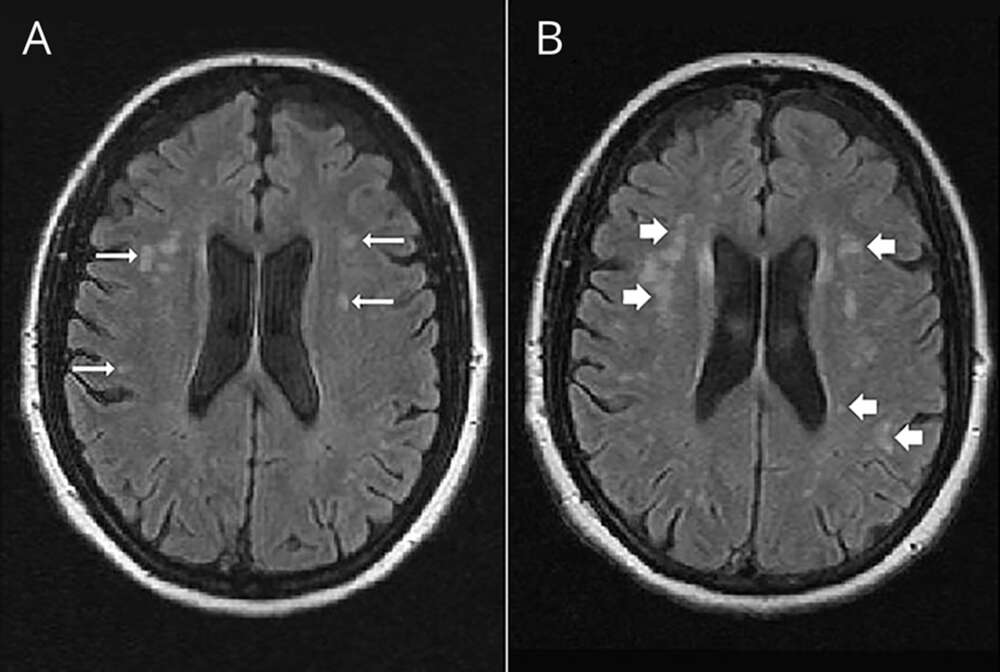

بستن PFO با اینترونشن

بستن سوراخ بیضی قلب PFO با استفاده از اینترونشن

عوارض و خطرات PFO

PFO چه علایم و چه خطراتی می تواند داشته باشد؟

PFO چیست؟

باقی ماندن سوراخ بیضی بین دو دهلیز